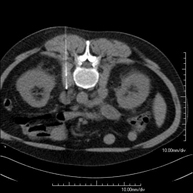

- Abdominal aorta CT angiography

A non-invasive diagnostic test that involves studying the abdominal aorta by obtaining high-definition anatomical images using CT (computed tomography) equipment and iodinated contrast. With the aid of workstations specialised for arterial studies, the image quality supports 2D and 3D reconstructions. It is indicated in patients with vascular disease (atherosclerosis), aortic aneurysms, abdominal pain of possible vascular origin, pre-surgical studies of lesions adjacent to the abdominal aorta as a vascular ‘map’, etc. Information obtained non-invasively is indispensable for patients requiring percutaneous or surgical processing. In patients who only require tracking of vascular lesions, this technique is the non-invasive technique of choice, together with MRI angiography.